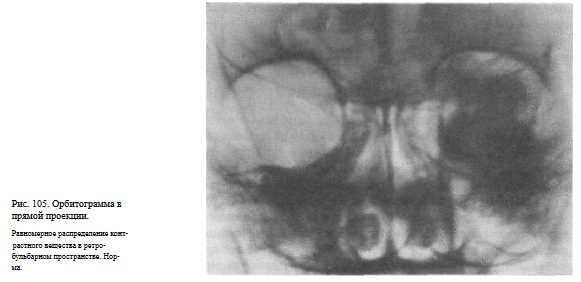

ОРБИТОГРАФИЯ

Назначение исследования — выявление объемного процесса в орбите путем контрастирования заглазничного пространства.

Методика исследования. Под местной анестезией вводят иглу через нижнее веко параллельно нижней стенке глазницы на глубину 1,5—2 см, и через нее вливают в теноново пространство 2—3 мл 0,5 % раствора новокаина, а затем 4—5 мл 20 % раствора гипака. Рентгенограммы выполняют через 1 и 10 мин после введения контрастного вещества в прямой (задней) и боковой проекциях.

Информативность исследования. Контрастное вещество равномерно распределяется в жировой клетчатке заглазничного пространства и на снимках в норме имеет типичную конфигурацию: на прямом снимке — форму прямоугольника с закругленными краями и округлым дефектом наполнения в центре в месте прохождения зрительного нерва (рис. 105), а на боковом снимке — конусовидную форму с полусферическим вдавлением в области основания, соответственно заднему полюсу глазного яблока.